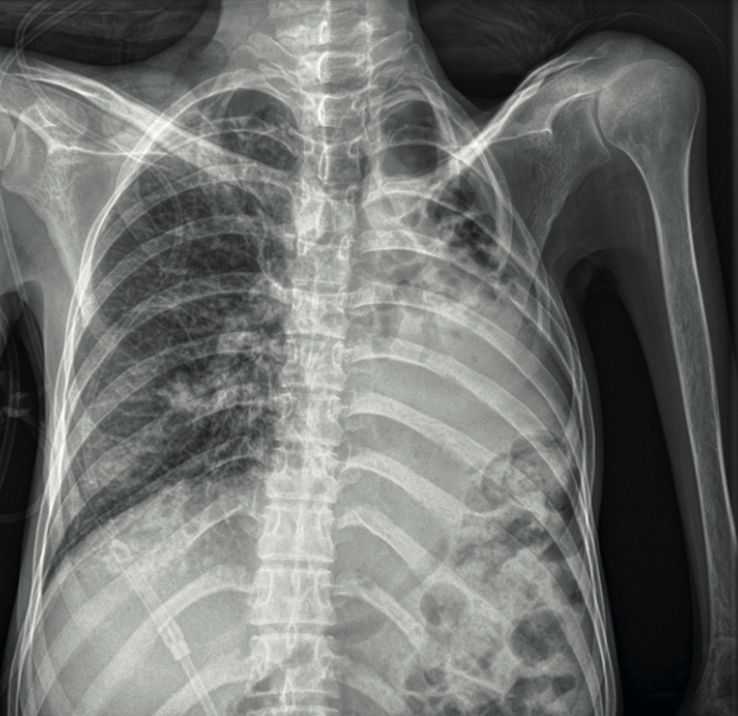

Se determinó la necesidad de atención médica multidisciplinaria, en coordinación con los servicios de neumología, genética, reumatología, cirugía plástica, nutrición clínica, oftalmología y epidemiología. La hipertensión arterial pulmonar se excluyó con base en el ecocardiograma, radiografía de tórax y angiotomografía torácica. En esos estudios se identificaron hallazgos compatibles con tromboembolia pulmonar, evidenciada por el defecto de llenado central en el tronco del lóbulo basal derecho (Figura 2). La anticoagulación se inició con 1 mg/kg de enoxaparina.

<strong>Figura 2</strong>

Figura 2. Radiografía de tórax al ingreso. Hiperclaridad en la región pulmonar basal derecha y discreta disminución de la trama vascular, hallazgos compatibles con alteraciones en la perfusión sugerentes de evento tromboembólico. Pulmón izquierdo con destrucción heterogénea del parénquima y cambios fibróticos, quizá secundarios a daño estructural crónico.